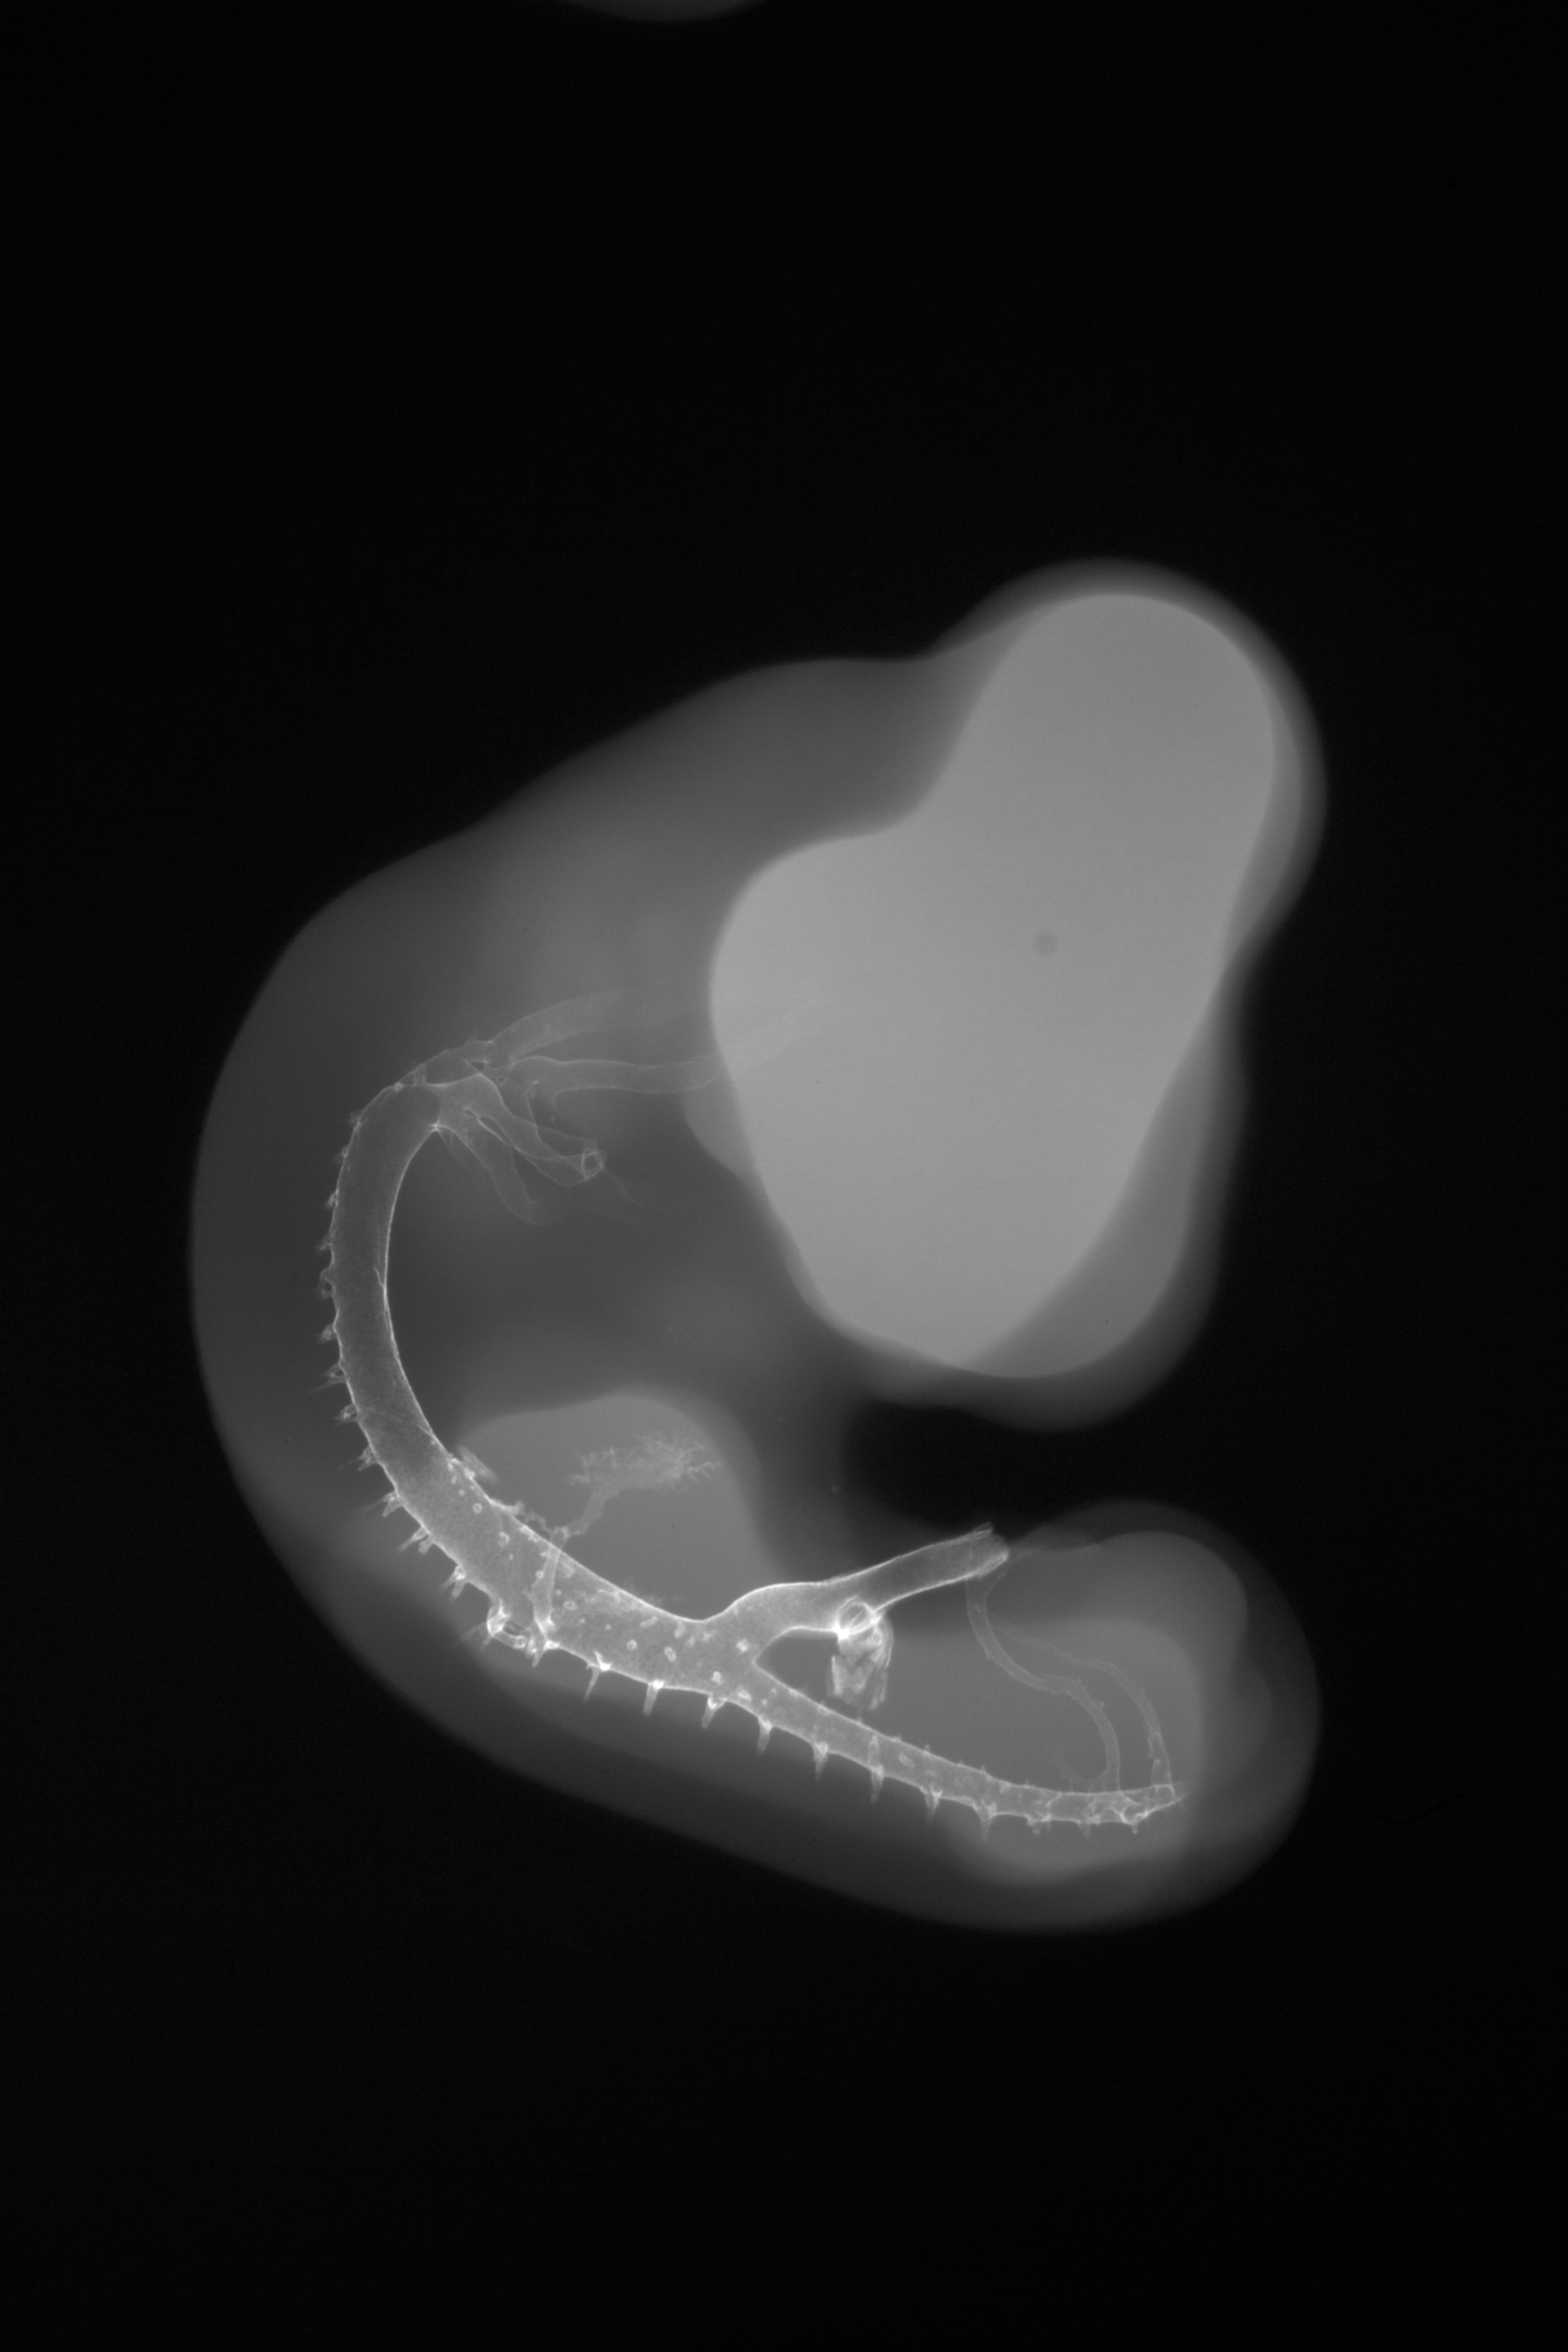

Chick Embryo Microangiography

Hamburger-Hamilton (HH) Stage 24 (approx. 4 - 4.5 days)

X-Ray Micrographs